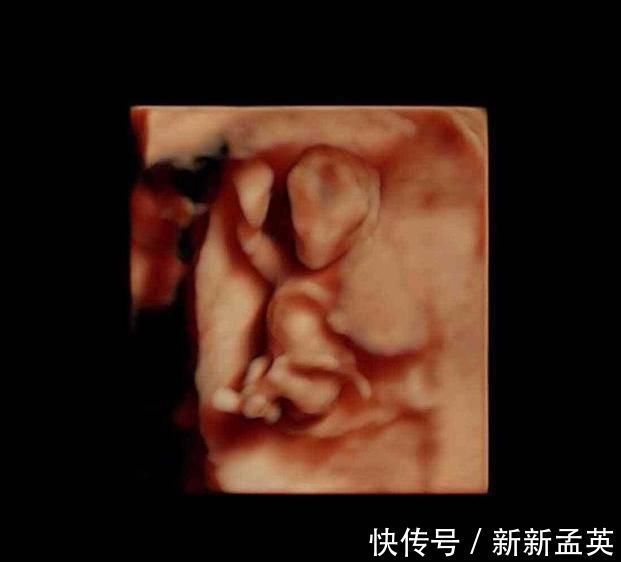

此时的胎儿继续快速发育,器官已经不是模糊一片,而是具有了鲜明的特征,比如手指脚趾已经形成,耳朵和牙齿也在发育,消化器官也开始发育了,基本都在定向地发展。